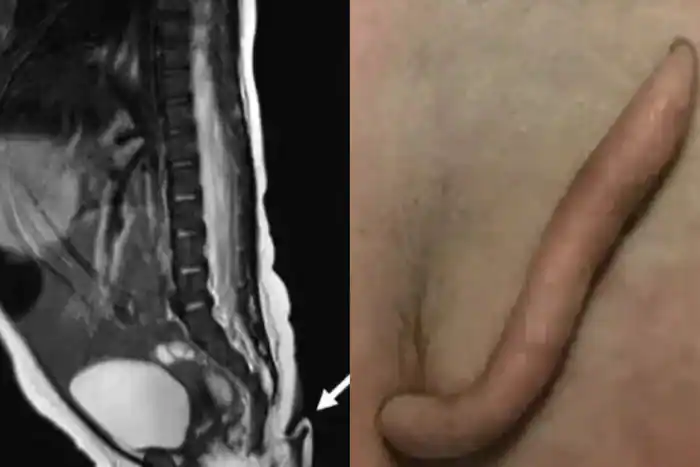

As per reports, the baby girl was born by a C-section at a hospital two months back in Nuevo Leon. She was born with the tail sticking out at the end of her tailbone with its base slightly to the left.

The tail is described as a “soft” 5.7-centimetre-long back end “covered in skin and fine hair.” It had a “pointy” tip and varied from 3mm and 5mm in diameter, narrowing towards the bottom. Soon after the news surfaced, images of the tail went viral on social media platforms.